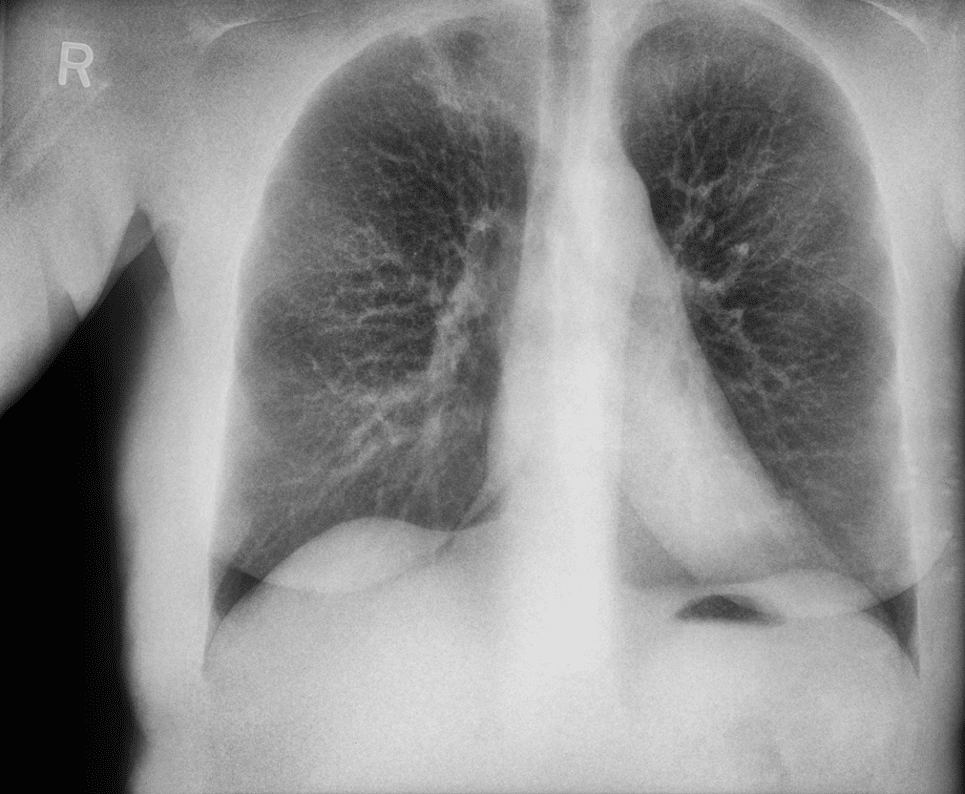

Pneumothorax Evaluation

Soft-tissue images reduce rib overlap and may improve visualization of pneumothorax in trauma patients.